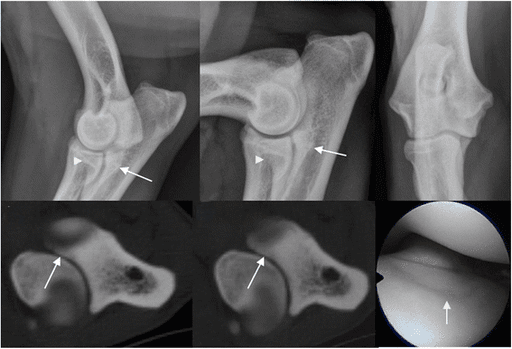

X-rays of the elbow are typically the first diagnostic tool and may reveal fragments, incongruity, or arthritic changes. CT scans or arthroscopy (minimally invasive joint exploration) may be recommended for detailed evaluation, particularly in young patients with mild signs or minimal radiographic changes.

UAP

OCD

FMCP